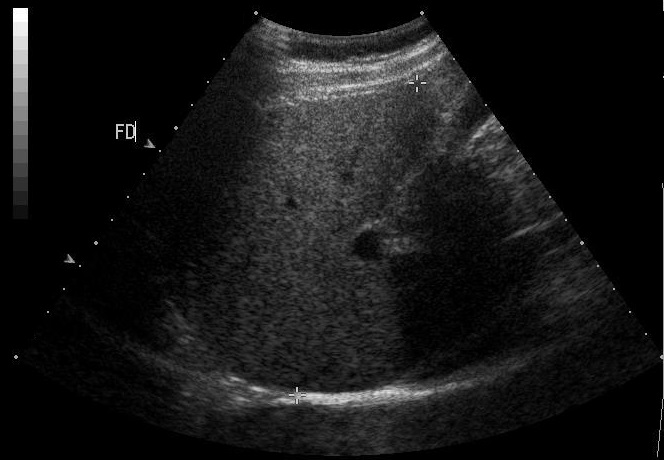

Coupe long sagitale mrdio-claviculaire a travers bord anterieure du foie , la

vescule biliaire au sinus costo diapragmatique droit

en arriere , la bifurcation de la veine porte .Le

point anterieuse du bord anterieuse du foie et au

point posterieuse est la mesure echographique du

foie droit , nosmalement 150mm |

Image echographique normale

du foie droit en coupe intercostale de

la ligne axilaire anterieuse droit ( long sagitale -

vesiculaire ) . On en

voyait foie droit , branche droit de la veine porte

, vesicule biliaire et artere hepatique |